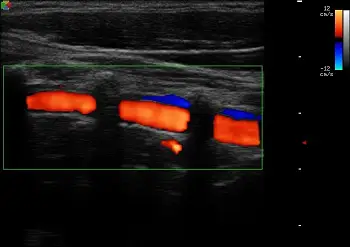

附圖是正常人體頸部彩色都卜勒影像,其中橘紅色部分為下列那一條血管?

頸部彩色都卜勒超音波(color Doppler ultrasound)可區分頸部各主要血管。本題考查椎動脈(vertebral artery)在超音波影像上的特徵性表現——其於頸椎橫突孔間走行,在彩色都卜勒影像中呈現被橫突聲影間隔的橘紅色節段性血流訊號,為辨識椎動脈的關鍵特徵。

影像為頸部彩色都卜勒超音波縱切面影像。影像框(color box)內可見多段鮮豔橘紅色的血流訊號,各節段之間由數個暗帶(acoustic shadowing,聲影)規律地間隔分開。這些暗帶即是頸椎**橫突(transverse processes)產生的強聲影,橘紅色的血流節段則是在橫突孔(transverse foramina)之間穿行的血管。此種「橘紅色血流被橫突聲影規則間隔」的外觀,正是椎動脈(vertebral artery)**的典型彩色都卜勒特徵。橘紅色代表血液朝向探頭方向流動(由下向上朝腦部方向),與正常順行性椎動脈血流方向一致。影像右緣可見少量藍色訊號,代表椎靜脈(vertebral vein)中的血流方向相反(離開探頭)。